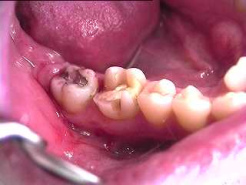

Backenzähne mit

Amalgam. Das Quecksilber dringt in die

Zahnsubstanz hinein und von dort weiter in

den Kieferknochen, denn Zähne sind nicht so

dicht, wie man allgemein meint

Backenzähne mit Amalgam. Das Quecksilber dringt in die Zahnsubstanz hinein und von dort weiter in den Kieferknochen, denn Zähne sind nicht so dicht, wie man allgemein meint